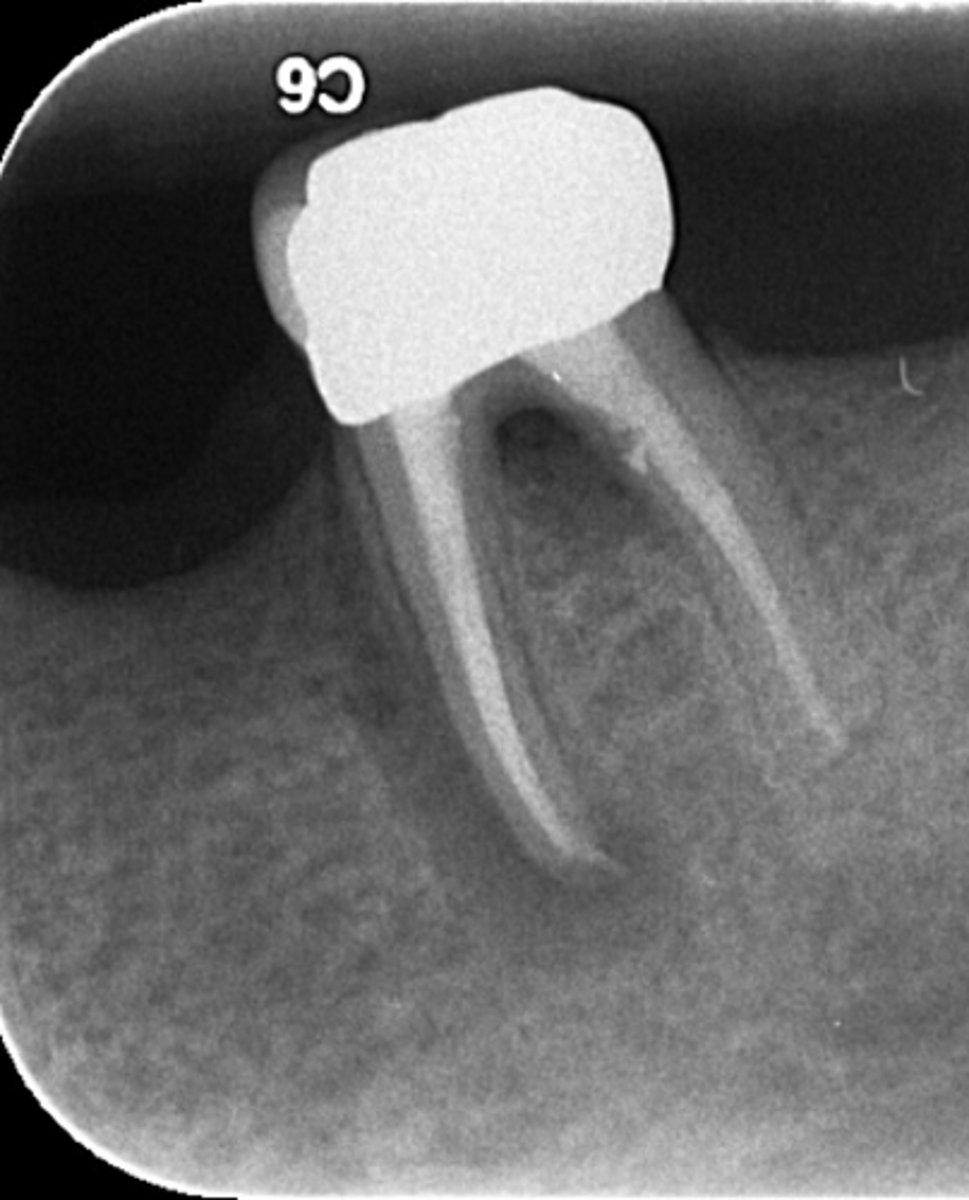

ID the problem:

splitting canals

fracture